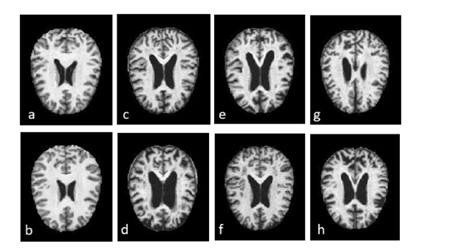

MRI images of Dementia cases in Figure 3, 4. AD leads to hippocampal atrophy and ventricular enlargement, healthy brain and brain images with AD are given in Figure 5 in an elderly, cognitively normal (CN) individual, an individual with amnestic mild cognitive impairment (aMCI) and an individual with Alzheimer's disease (AD) by obtaining images from the relevant literature.

Figure 3: MRI images of dementia cases (a,b) Non-dementia, (c,d) Very mild dementia, (e,f) Mild dementia, and (g,h) Moderate dementia [59].